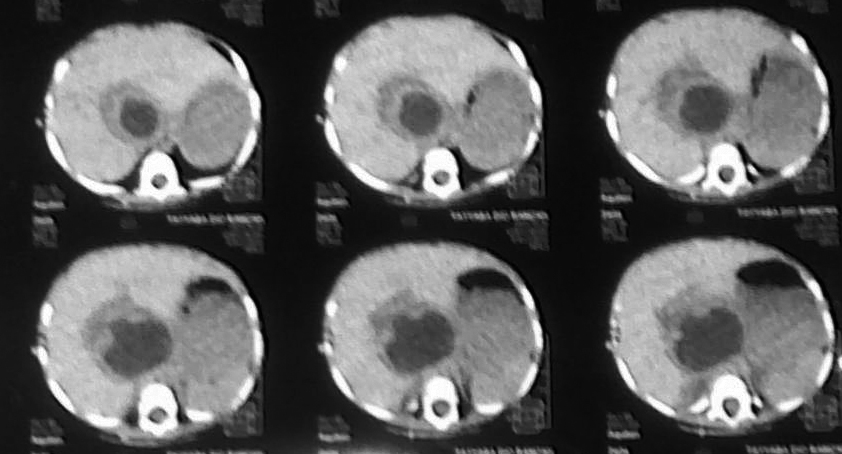

A 1-year-old female child presented with distention of abdomen, accompanied with occasional episodes of vomiting and abdominal pain for the past eight months with no history of constipation or fever. The child was vitally stable. On inspection upper abdomen was found distended and mild tenderness in epigastrium on deep palpation. Laboratory investigations were within normal limits. The plain radiograph of abdomen was unremarkable. Ultrasound scan showed a 6.9 cm x 7.5 cm sized cystic area with internal debris at porta hepatis, compressing the liver. CT scan showed a 5 cm x 7 cm sized cyst extending from porta hepatis to the duodenum (Fig. 1). The preoperative differentials were duodenal duplication and choledochal cyst.

Figure 1: CT scan showing a hypo-dense area at porta hepatis.